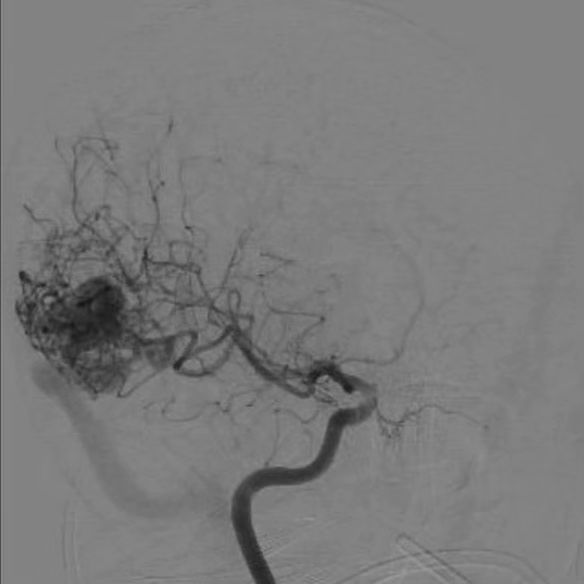

Em fevereiro deste ano, durante mais uma crise de enxaqueca, com uma dor muito mais intensa do que de costume, fui a um hospital acompanhada por minha mãe, que é enfermeira. Lá, um médico sugeriu testar uma medicação para dor, internada, para monitorar possíveis reações alérgicas. Ele também solicitou uma tomografia e a avaliação de um neurologista. O exame mostrou uma mancha, e o neurologista pediu duas ressonâncias, que confirmaram o diagnóstico de MAV, uma malformação congênita arteriovenosa cerebral.

Começou então uma corrida contra o tempo em busca de um neurocirurgião vascular que tratasse meu caso. O convênio de saúde forneceu uma lista de profissionais, mas nenhum era especialista em MAV. Após muita pesquisa, encontrei um médico em São Paulo, referência no país, que me deu esperança e falou sobre a cirurgia para a retirada da MAV. Esta malformação rouba o fluxo sanguíneo que deveria ir para meu cérebro, causando tonturas, desmaios, turvação visual, formigamento, dor torácica e diminuição da força no meu braço esquerdo.